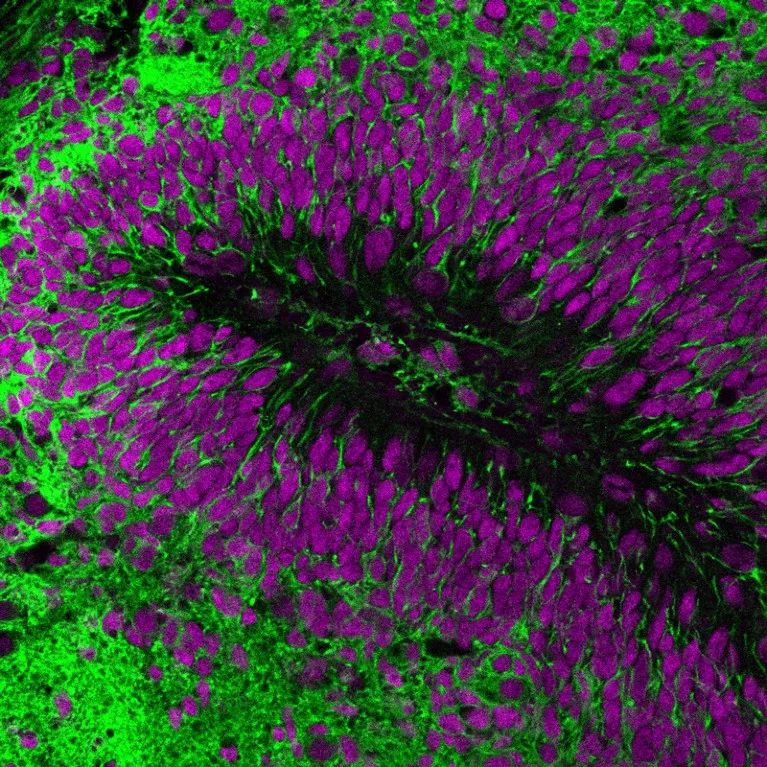

科学家将人类类器官(亮绿色)移植到小鼠大脑中,以研究神经元细胞在健康和疾病背景下的细胞行为。来源:Abed Mansour